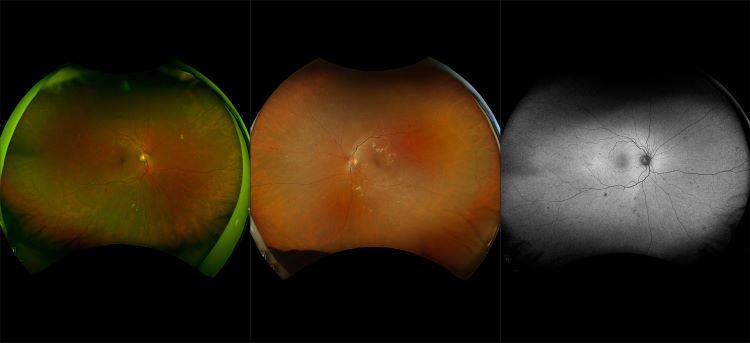

optomap Multimodal Diabetic Eye Disease Cases

Optos offers multimodal imaging with all ultra-widefield devices. Having both ultra-widefield and four images captured in less than one second has been shown to enhance pathology detection and disease management as well as improve practice and clinic flow. Ultra-widefield multimodal imaging is important across all access points of patient care - screening, detection, diagnosis, and treatment.